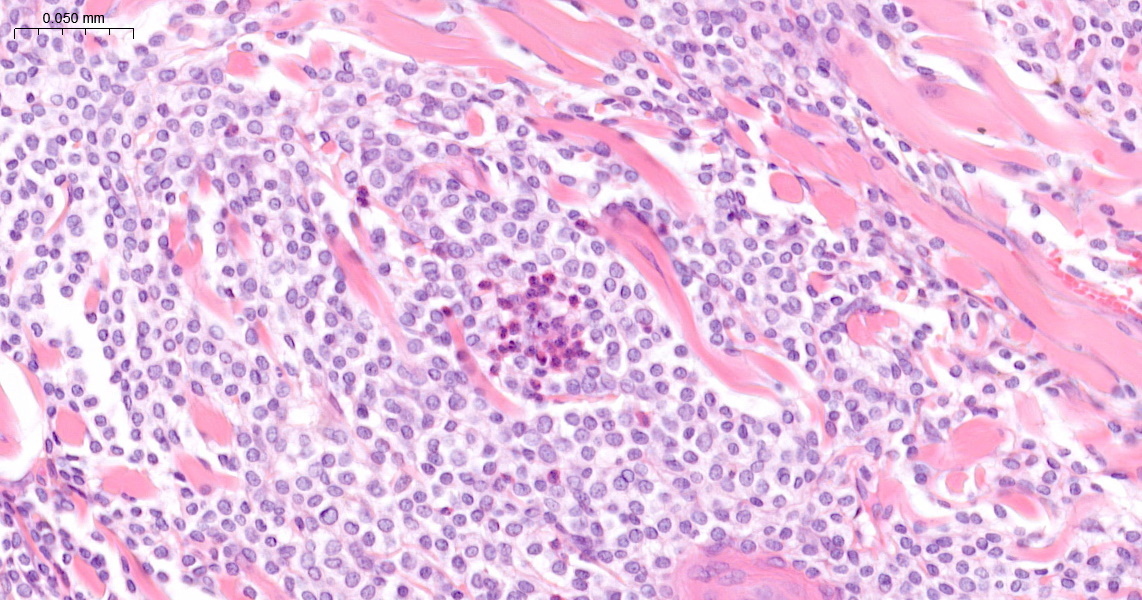

The mass was densely cellular, with tightly packed uniform round cells showing fine, pale intracytoplasmic granules. Occasional eosinophils were intermixed within scant stroma (Figure 2). There was no nuclear atypia, and mitotic activity was low, typically zero to two mitoses per high-power field (x400). The mass was not encapsulated but had been completely excised together with the underlying panniculus muscle.

The lesion was diagnosed as a cutaneous mast cell tumour based on the lesion’s architecture and cytological features.